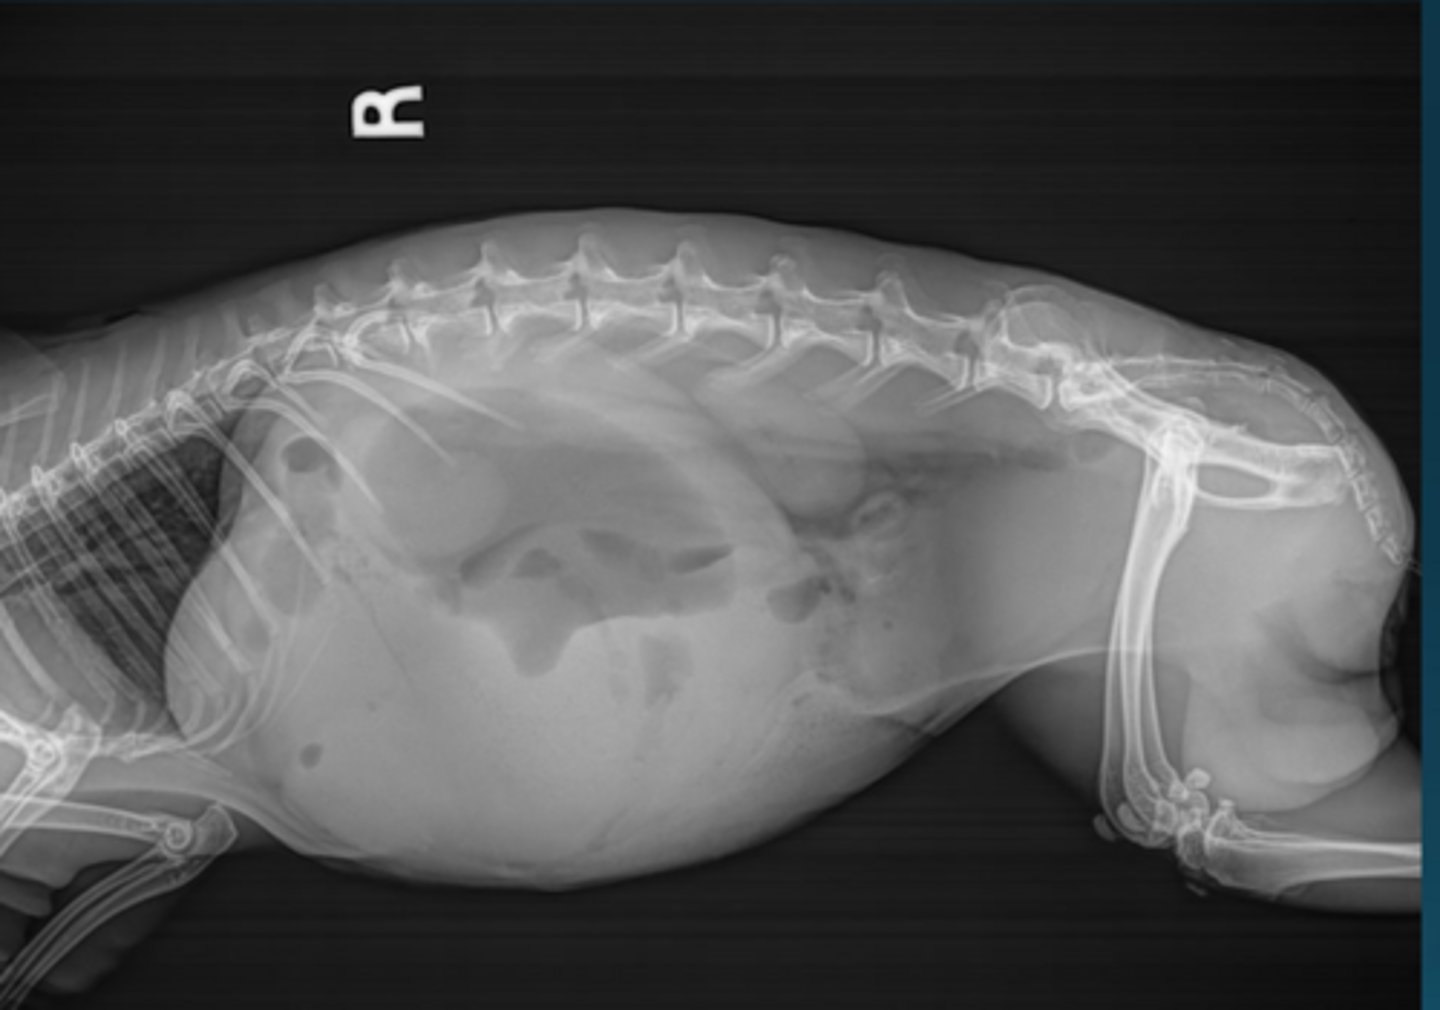

Normal

Is this a normal OR abnormal rabbit?

The caudal border of the stomach should not pass the caudal border of L2

How do you determine if the stomach is normal size on rabbit x-rays?

There is lots of gas in the cecum and the stomach is getting large.

Give IV fluids, syringe feed, lidocaine CRI

What do you want to do for this rabbit, who has recently been spayed?

Hyperglycemia associated with GI obstruction. This patient is also hypothermic.

Give thermosupport, surgery, may sedate and pass orogastric tube to relieve pressure in stomach

This rabbit has a temperature of 98.1 F. There is a firm, cranial abdominal mass. The bloodwork is normal apart from hyperglycemia of 641. What is likely happening here and how do you treat?